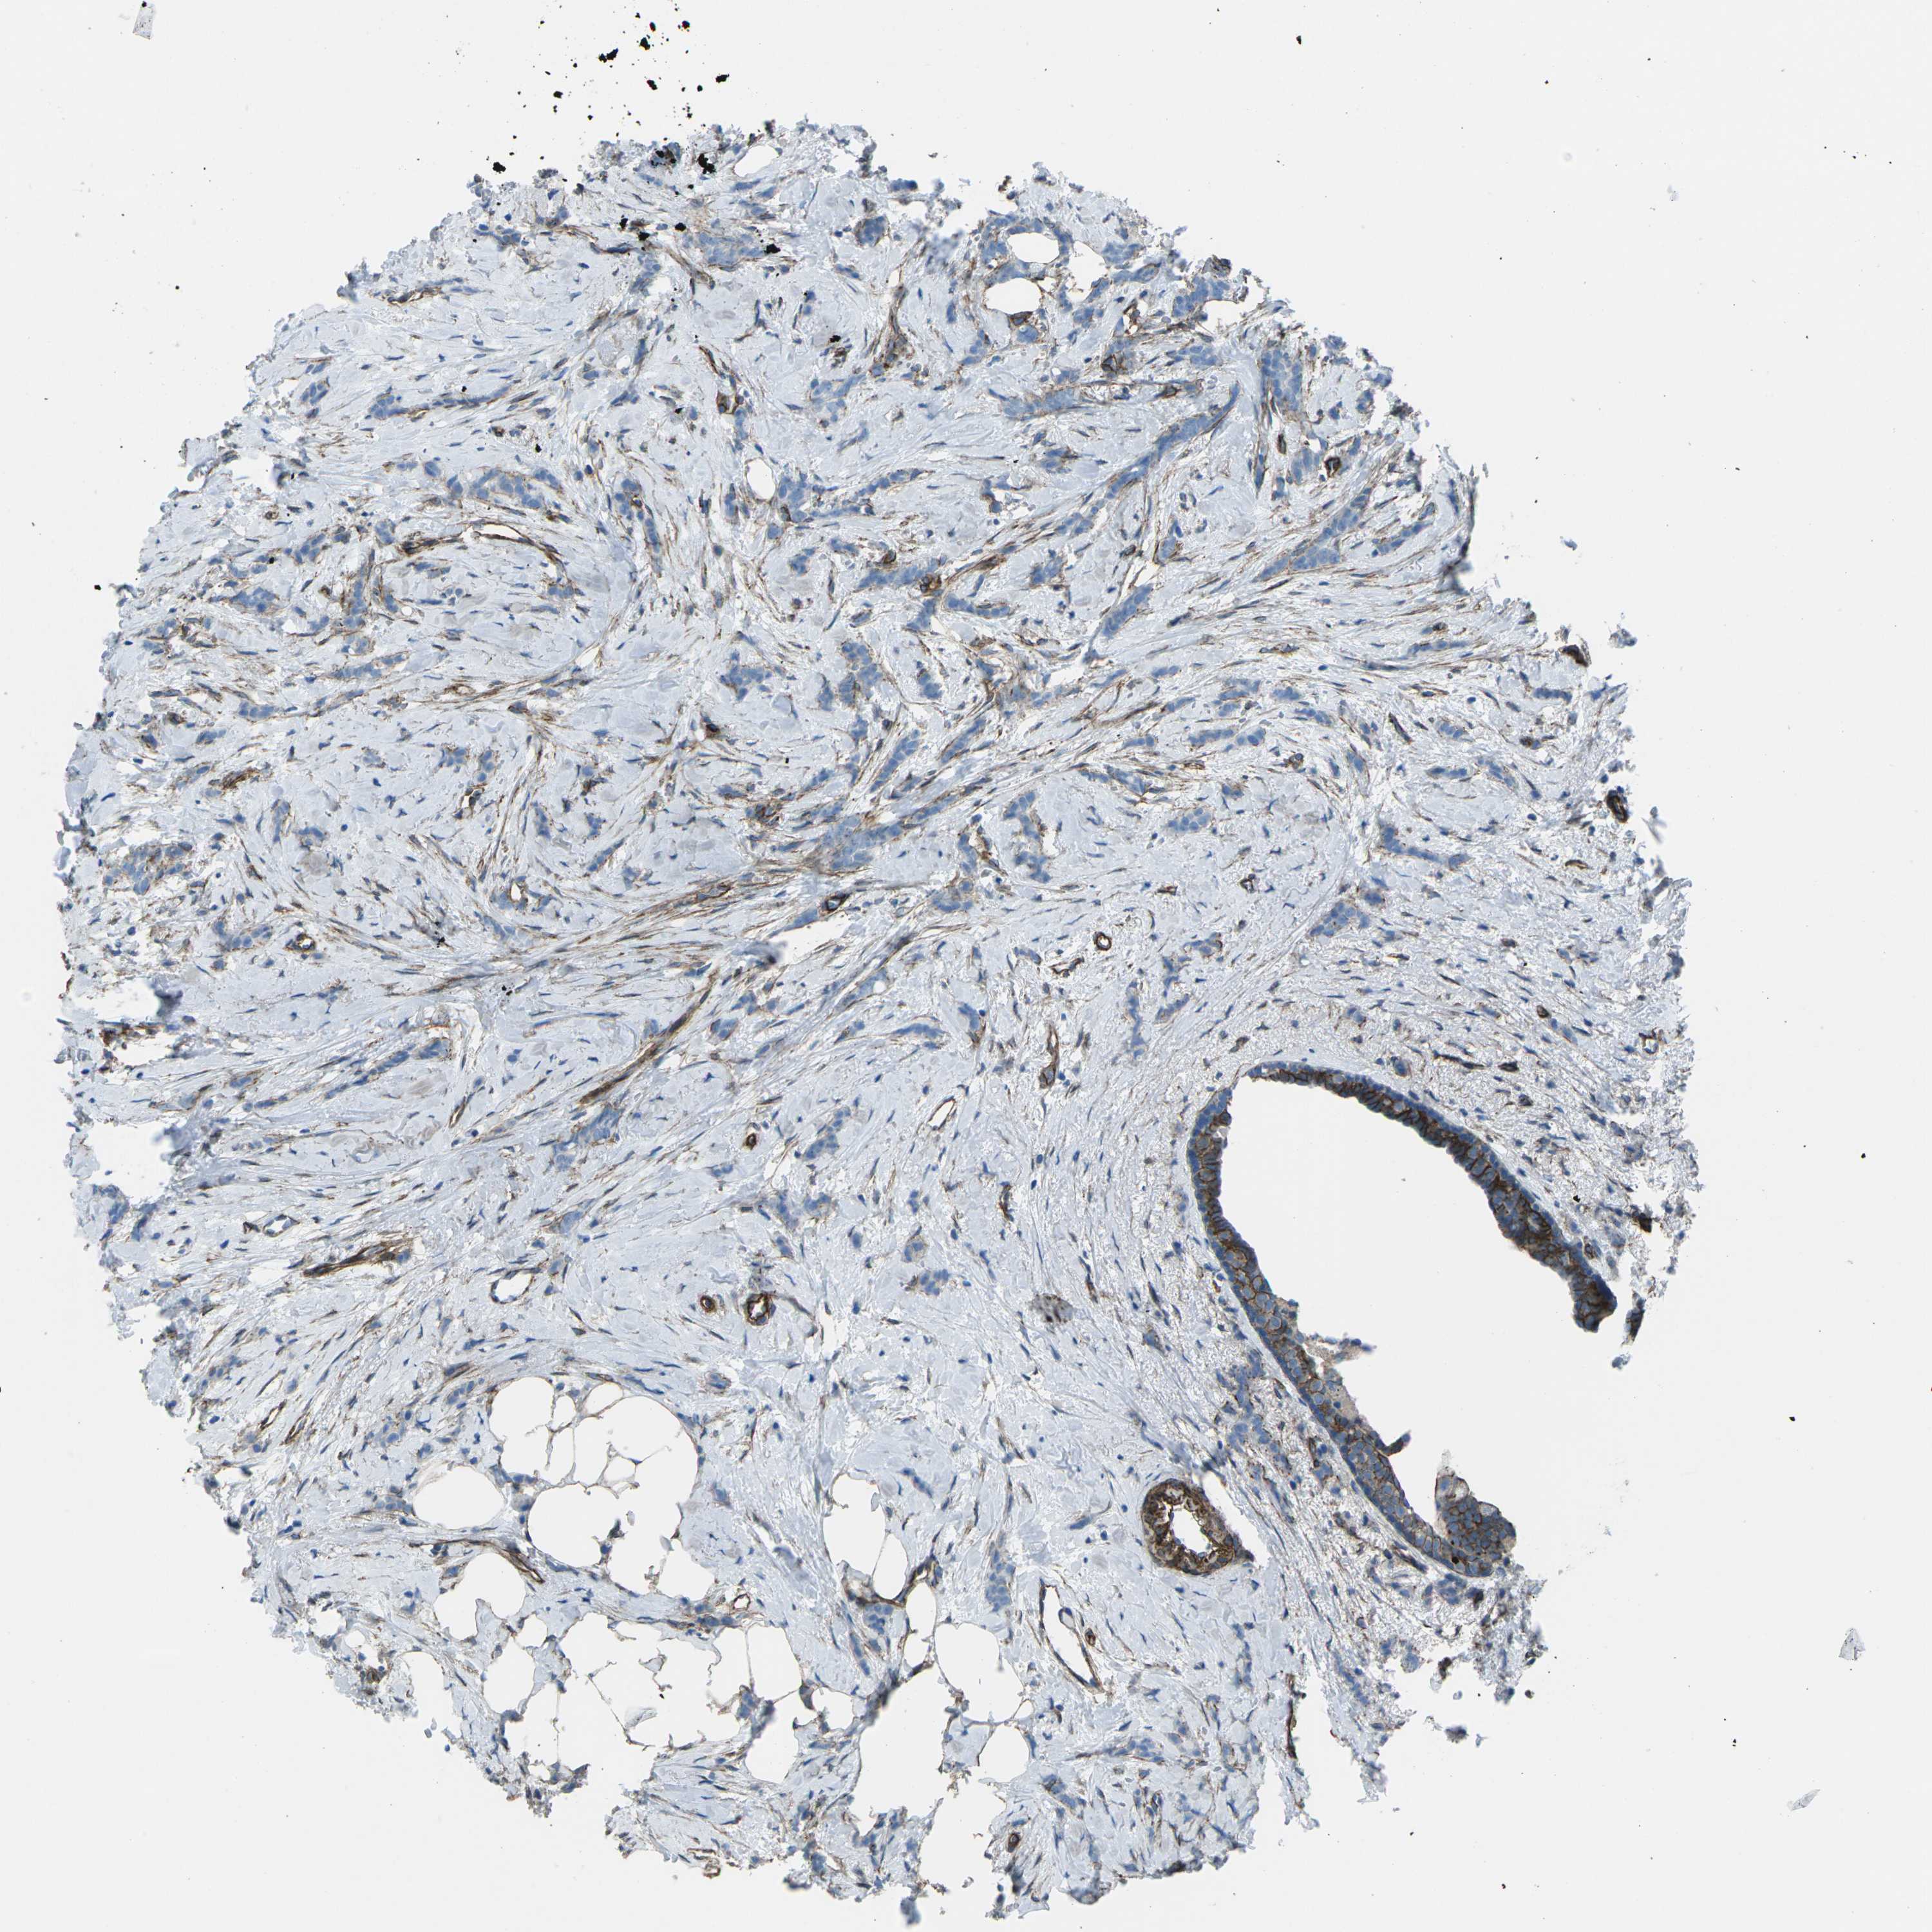

BRCA TCGA BRCA VALIDATION PROTEIN EXPRESSION

ANTIBODIES

AND

VALIDATION